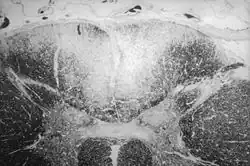

| Axial section of the spinal cord showing syphilitic destruction (whitened area, upper center) of the posterior columns which carry sensory information from the body to the brain | |

Tabes dorsalis is a late consequence of neurosyphilis, characterized by the slow degeneration (specifically, demyelination) of the neural tracts primarily in the dorsal root ganglia of the spinal cord (nerve root). These patients have lancinating nerve root pain which is aggravated by coughing, and features of sensory ataxia with ocular involvement.

Tabes dorsalis is caused by demyelination by advanced syphilis infection (tertiary syphilis) when the primary infection by the causative spirochete bacterium, Treponema pallidum, is left untreated for an extended period of time (past the point of blood infection by the organism).[3] The spirochete invades large myelinated fibers, leading to the involvement of the dorsal column medial leminiscus pathway rather than the spinothalamic tract.